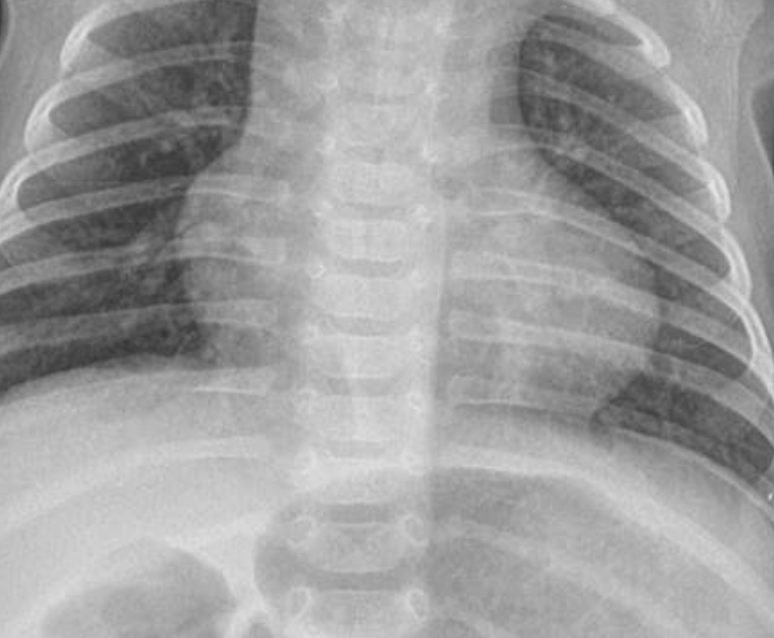

- Preterm 29 weeks gestation C/S delivery showed severe respiratory distress soon after birth - RDS

- Air bronchograms

There is a homogeneous opacification of both lungs with white-out lungs - (1 .field (grounds glass appearance) and air bronchogram bilaterally

.The diagnosis is Acute Respiratory Distress Syndrome (ARDS) - (2

- .I- Massive blood transfusions Preterm 29-weeks gestation C/S delivery showed severe respiratory distress soon after birth. This chest x-ray was taken at the age of 6 hours.

- Q1: Write 2 abnormalities in the X-Ray?

- Q2: What is the likely diagnosis?

- Q1: Ground glass appearance, wide intercostal space.

- Q3: Mechanical ventilation, give Surfactant for lungs maturation.